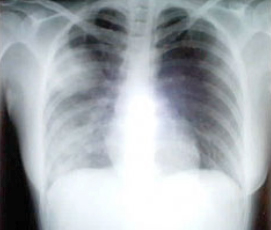

SARS患者患病三天的胸透照片